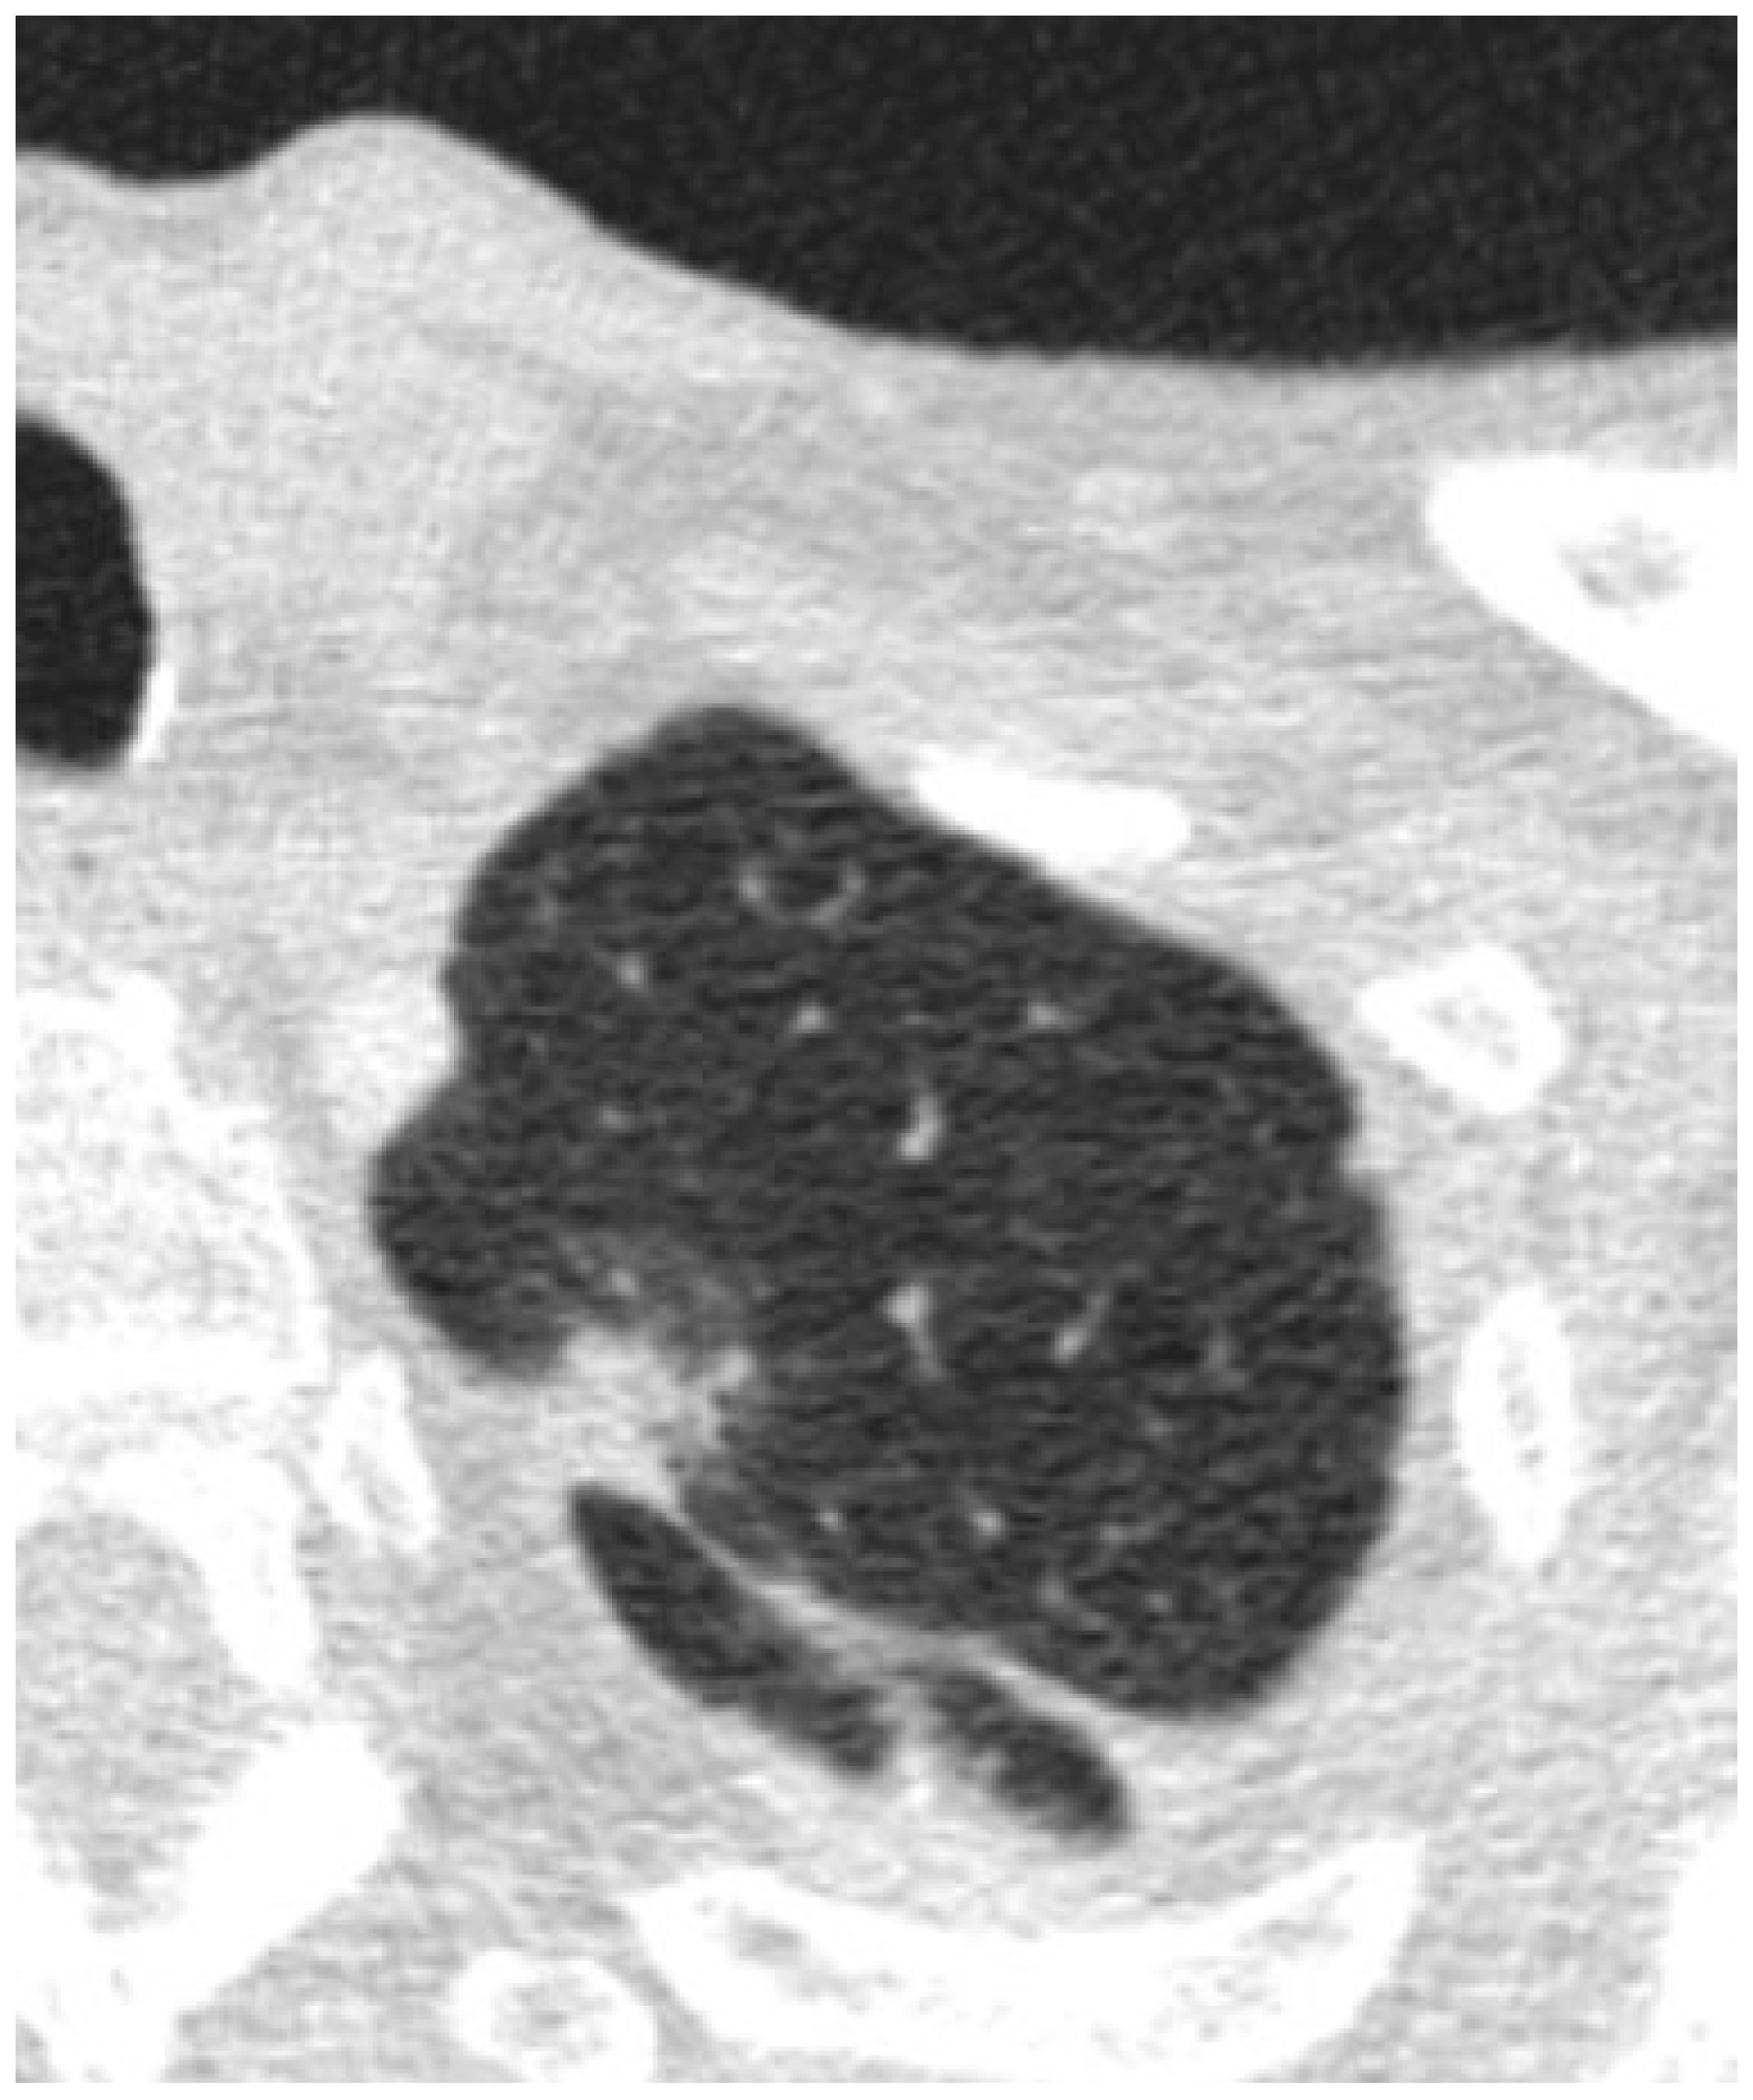

Predicting Invasiveness in Lepidic Pattern Adenocarcinoma of Lung: Analysis of Visual Semantic and Radiomic Features

3.1. Visual Read Variables

3.2. Radiomic Variables